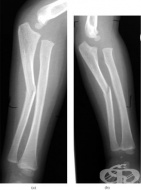

S52.2 Счупване на тялото [диафиза] на лакътната кост

Заболявания

Увредите на тялото на лакътната кост са много чести и по-често се срещат при мъжете, което се дължи ...

S52.3 Счупване на тялото [диафиза] на лъчевата кост

Счупване на тялото [диафиза] на лъчевата кост са сравнително чести и са характерни за юношеската и м...